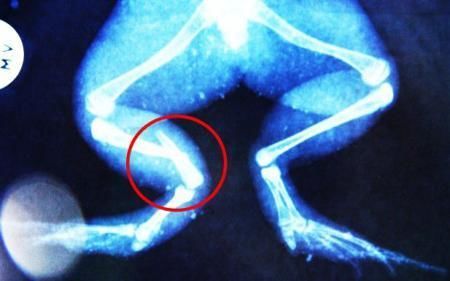

環(huán)球網(wǎng)4月2日?qǐng)?bào)道 據(jù)《每日郵報(bào)》報(bào)道,上個(gè)月,南非大牛蛙布魯萊的右小腿被鄰居家的一只狗咬到,導(dǎo)致粉碎性骨折,現(xiàn)在經(jīng)過2個(gè)小時(shí)的手術(shù),它的斷腿已經(jīng)被接上,它也因此成為有史以來第一只通過外科手術(shù)用鋼針接上斷腿的青蛙。

野生生物專家安妮經(jīng)常為學(xué)校寫教材,她認(rèn)為這是人類第一次通過手術(shù)給一只青蛙接斷腿。在手術(shù)開始階段,獸醫(yī)把少量給狗用的麻醉藥注入到這只青蛙體內(nèi),讓它失去知覺。然后他在布魯萊的斷腿上切開一個(gè)小口,把一根小鋼針植入腿里。最后獸醫(yī)給它縫了9針,把切口縫合在一起。僅僅幾周后,布魯萊就能在安妮家附近活動(dòng)了。這只青蛙大約已有25歲,主要以嚙齒動(dòng)物、蛇和其他青蛙為食。布魯萊所屬的牛蛙種群正在不斷減小,目前只能在非洲南部的濕地里才能看到這種青蛙。